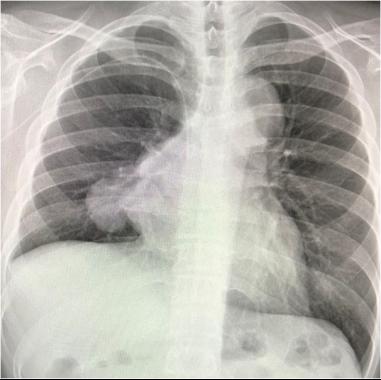

起初魏先生只是反复发烧和咳嗽,前往社区诊所检查以为只是普通感冒,直到2个月后,依旧反复不见好转,检查血氧后发现远远低于正常值范围,于是在医生建议下赶紧前往大医院拍胸片。“看到肺部发白的胸片结果,当时以为是肺炎或者肺结核,后面经过验血、CT一系列检查,才被确诊为得了血液肿瘤疾病,心情一下好失落。”魏先生回忆。